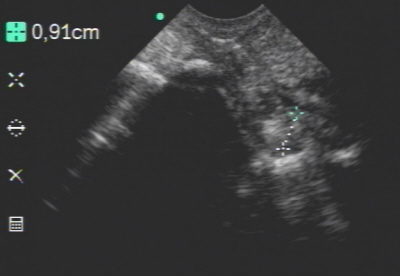

Oberes Strahlbeinband unauffällig